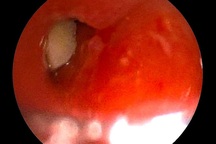

Đây là một trường hợp dị vật khá đặc biệt. Dị vật được lấy ra là một mảnh gỗ khá dài, khoảng 5cm, đã bị gãy thành hai mảnh. Bệnh nhân cũng không biết chính xác vì sao lại có mảnh gỗ này trong ổ bụng. Anh cho biết trước đó hai tuần mình có ăn kem, sau đó thì thấy bụng tăng dần.

“Đây có thể là mảnh của que kem hoặc cũng có thể là do vô tình nuốt tăm, chọc thủng từ đại tràng ra”, BS Bình cho biết.